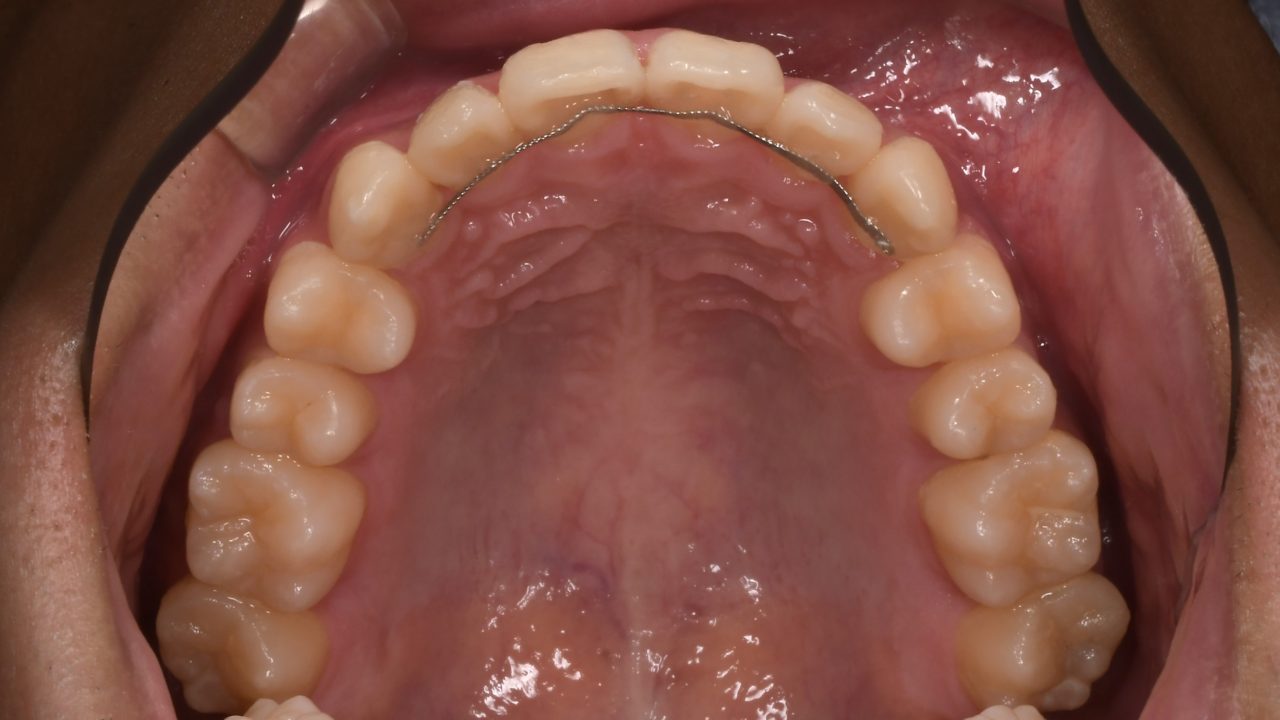

マウスピース矯正で治したい

Before

After

| 主訴 | 前歯の凸凹をマウスピース矯正で治したい |

|---|---|

| 診断 | 両側アングル1級叢生 |

| 矯正方法 | インビザラインによるマウスピース矯正 |

| 矯正期間 | 13か月 |

| 費用 | 890,000円(税別) |

| 調整料 | 5,000円(税別) |

| 備考 | 上下顎の前歯の凸凹を治したいという審美的な主訴でした。 以前に奥様が当院でインビザラインによるマウスピース矯正を受けられ終了しています。 その様子をふまえて、ご主人もマウスピース矯正を希望されました。 前歯の凸凹をまっすく並べるために上下顎共に左右に歯列を拡大しました。 特に上顎は狭い狭窄歯列でしたので、適正な広さに回復しました。 元々上下のバランスは悪くないので、非常にきれいな仕上がりとなりました。 銀歯もすべてセラミックに代え、ホワイトニングもしました。 |